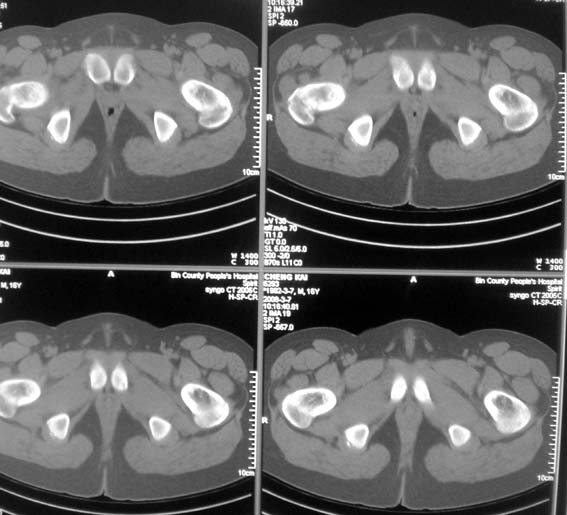

标题: CT12101:髋关节疼痛,请会诊。

男,16岁,髋部疼痛,发育延迟。

考虑:双侧髋臼发育不良性骨病。

双侧髋臼发育不良性骨病

双侧髋臼发育不良性骨病.股骨头早期坏死?

双侧髋臼发育不良性骨病(髋臼窝变浅,髋臼内上缘关节面毛糙)。